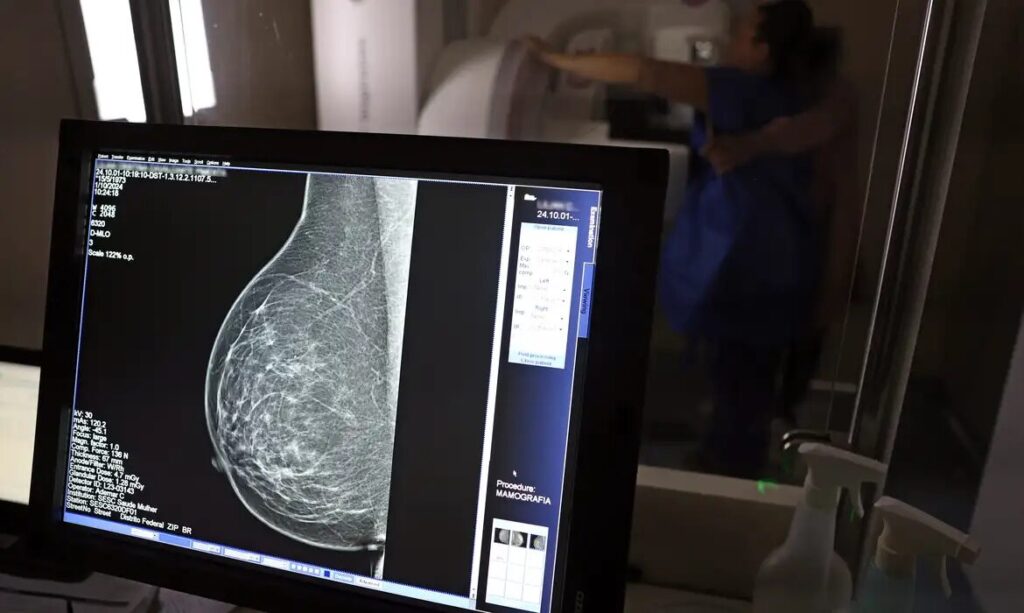

Faixa etária da mamografia é ampliada no SUS: exame passa a ser indicado até os 74 anos

O Ministério da Saúde (MS) anunciou nesta terça-feira, 23, a ampliação da faixa etária para o rastreamento do câncer de mama no Sistema Único de Saúde (SUS). A partir de outubro, o exame passará a incluir mulheres de 50 a 74 anos. Antes, o limite era de 69 anos. A novidade faz parte de uma série de novas recomendações para a detecção precoce da doença.

Mesmo sem sinais ou sintomas da doença, a cada dois anos, essas mulheres serão chamadas para realizar mamografias de forma preventiva. A pasta considera que o envelhecimento é um dos principais fatores de risco para o câncer de mama e segue as orientações da Organização Pan-Americana da Saúde (OPAS) e da Organização Mundial da Saúde (OMS), que recomendam a ampliação da cobertura para garantir diagnóstico precoce e maior chance de tratamento eficaz.